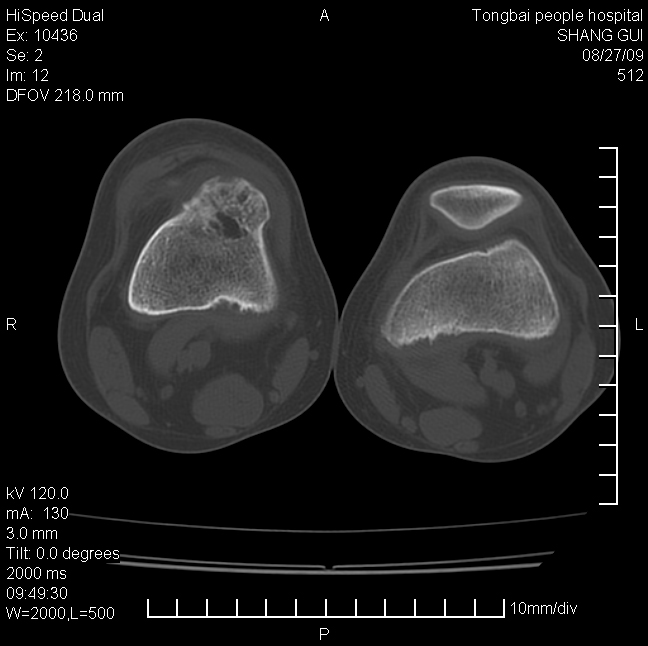

女,12岁。无意发现股骨下端隆起。局部皮肤颜色,温度无异常。

不能排除,其实平片更直观。宽基底骨软骨瘤皮质与骨干皮质相连,髓腔与髓腔相通,骨纹理走行方向一致,部分软骨帽可有钙化,本例病变内“磨玻璃状、多囊状改变”比较符合骨纤。